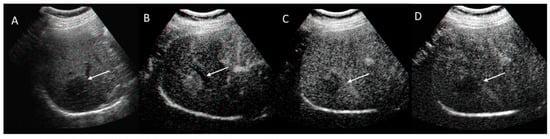

2.3. CEUS-LI-RADS

2.3.2. CEUS-LI-RADS Categories

2.3.3. CEUS-LI-RADS vs. CT/MRI LI-RADS